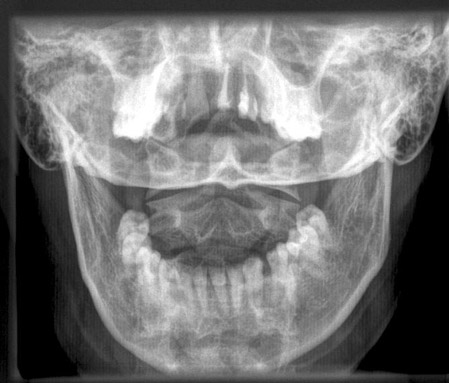

Dens a.p.

Fehler

Ungleicher Abstand der beiden aufsteigenden Unterkieferäste vom Dens.

Abhilfe

Der Kopf muss absolut symmetrisch zur Körperlängsachse gehalten werden.